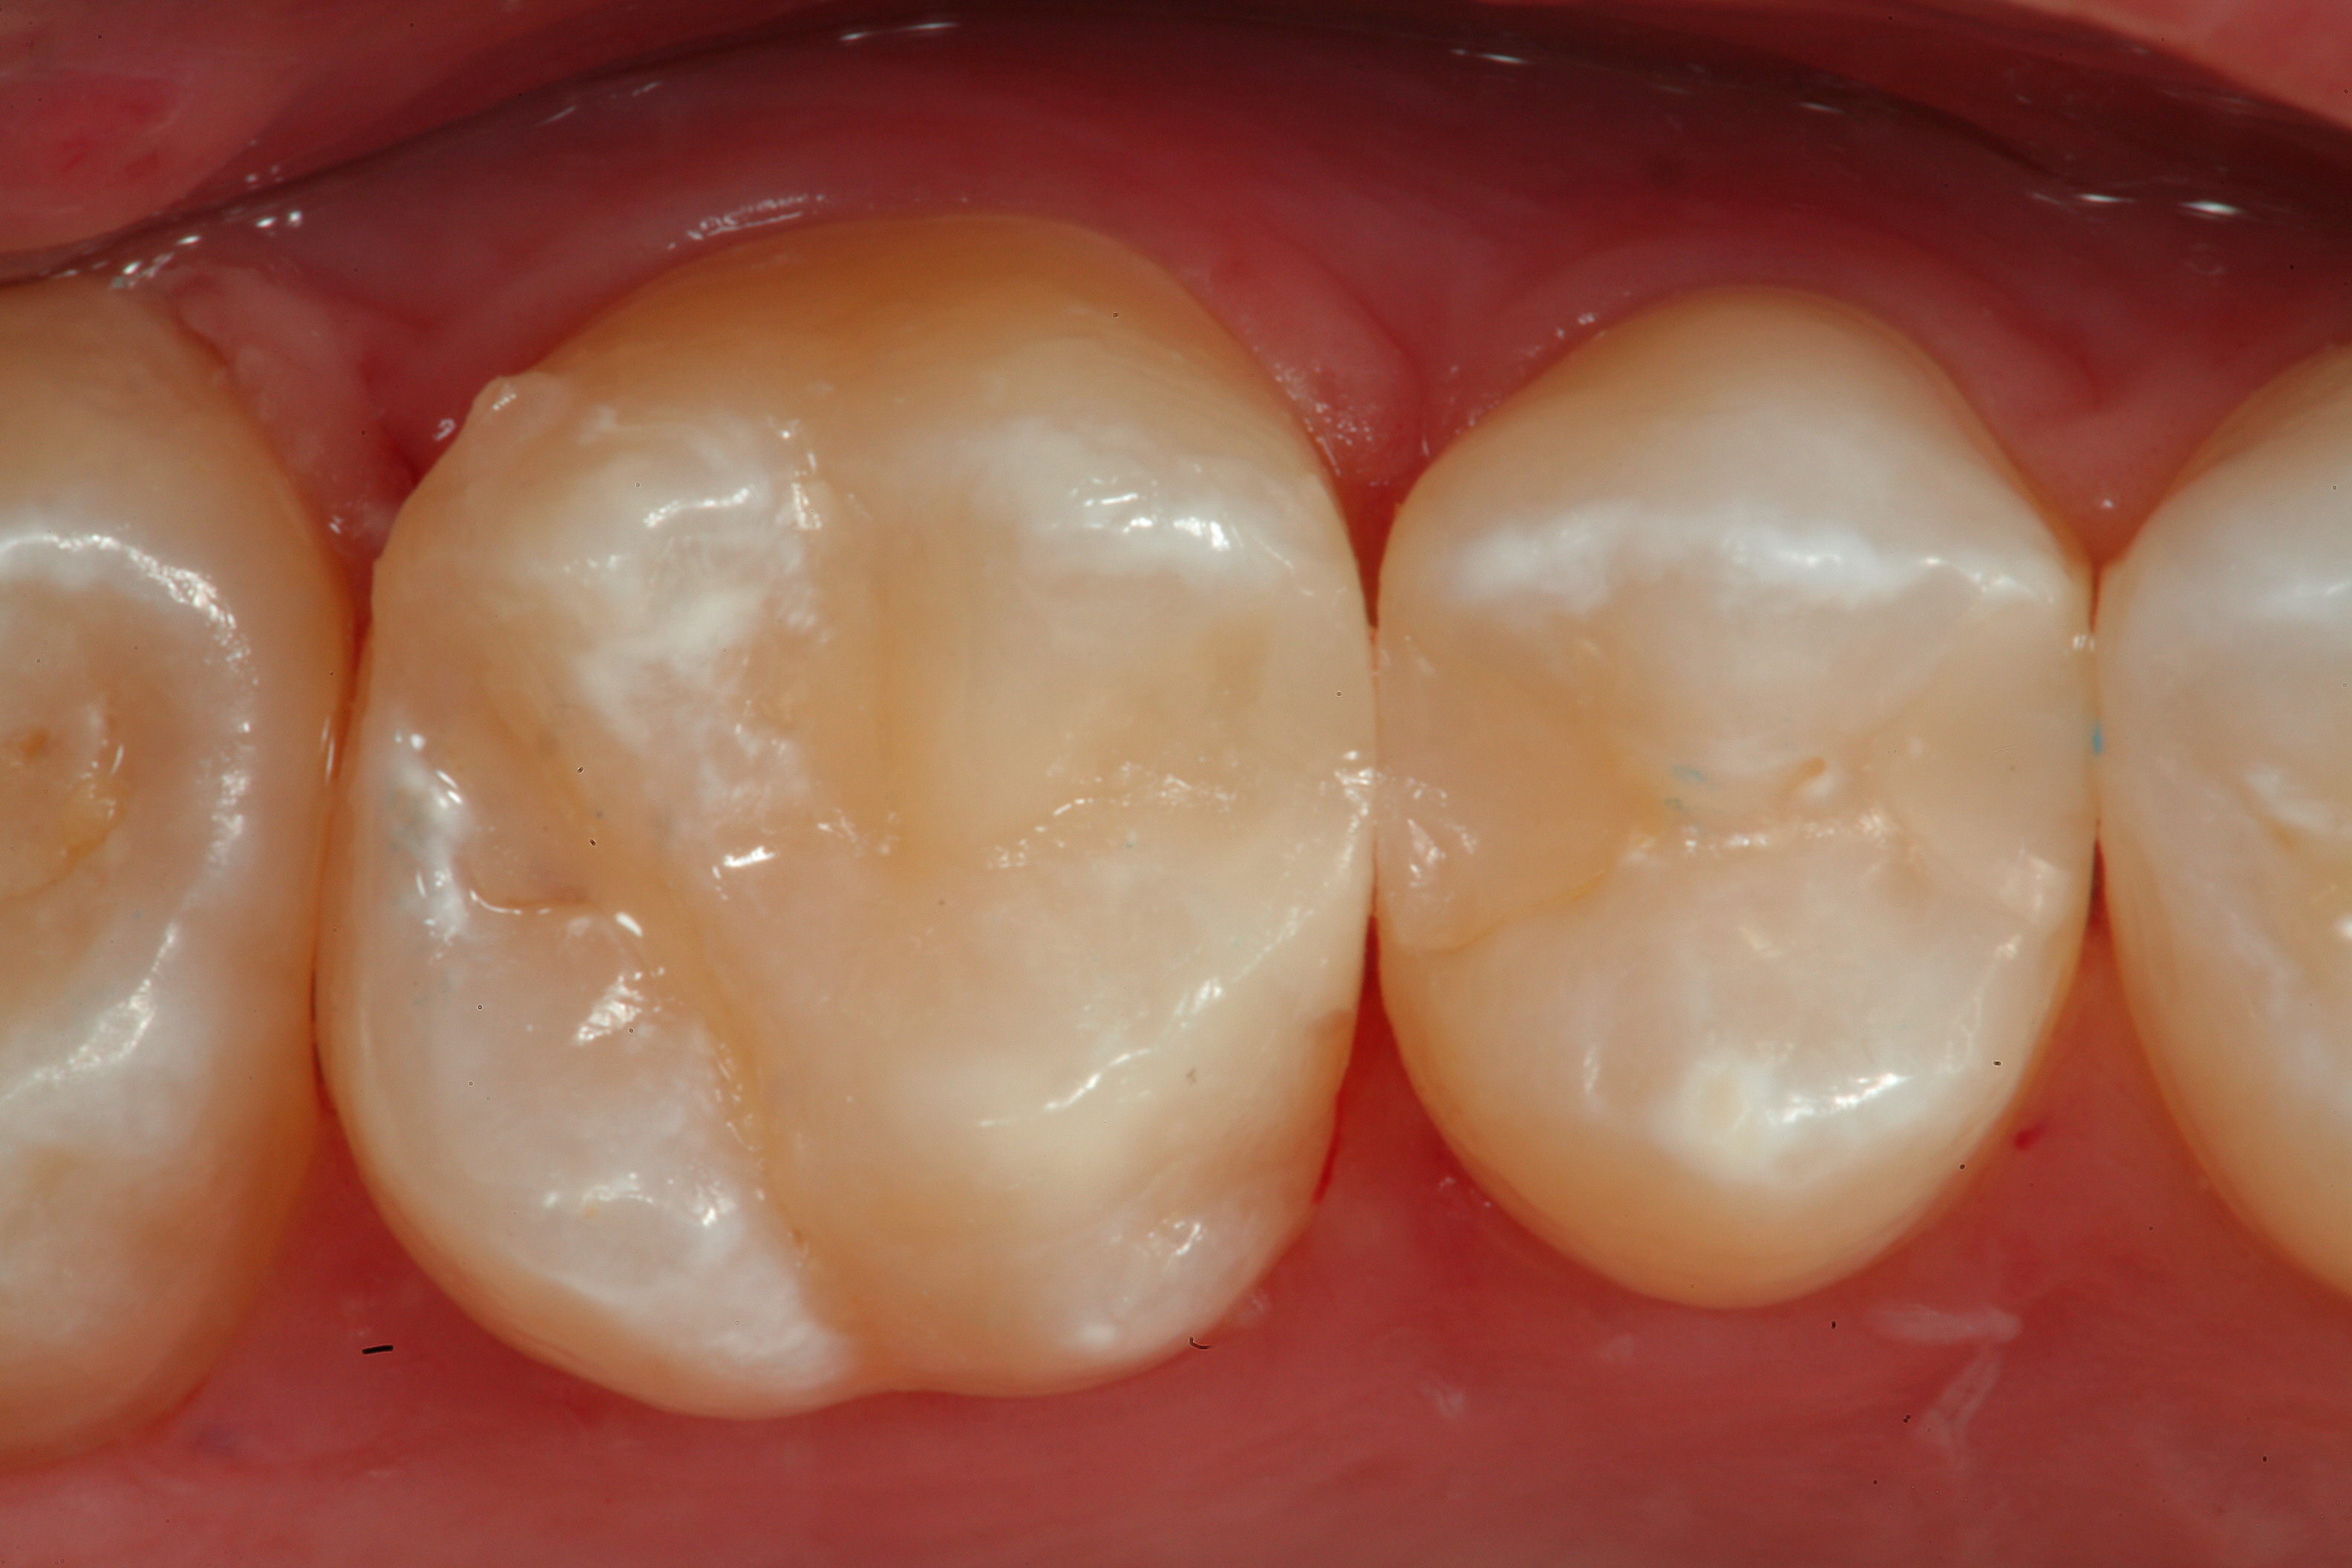

Fig 25. An occlusal view of the completed Giomer bulk-filled composite restorations on teeth Nos. 29 and 30.

Figure 25